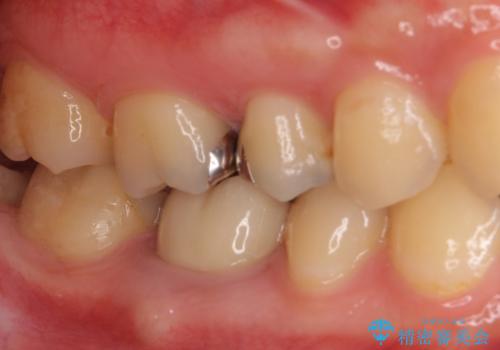

- 奥歯の銀歯の下にあるむし歯治療を希望して来院された患者様です。

口を開けたときに見えてしまう部分はセラミックインレーやジルコニアクラウンに、目立たない部分はゴールドインレーにてむし歯治療を行うこととしました。

機能面を優先すると、PGAインレー(ゴールドインレー)による修復治療やPGAクラウンによる補綴治療が望ましいのですが、笑ったときに見えている銀歯がどうしても気なってしまうとのことで、目立ってしまう奥歯はセラミックインレーやセラミッククラウンを装着することとしました。